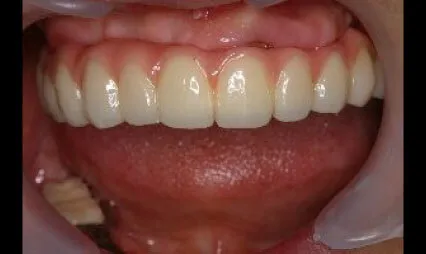

症例⑤

| 主訴 | 他院にて抜歯後、歯を入れたい |

|---|---|

| 診断名 | 歯根破折 |

| 年齢 | 21歳 |

治療に用いた装置(治療法) | インプラント |

| 部位 | 右上1 |

| 治療期間 | 5か月 |

| 治療費用 | 462,000円 |

| リスク・副作用(治療に関する) | 腫脹、しびれ |